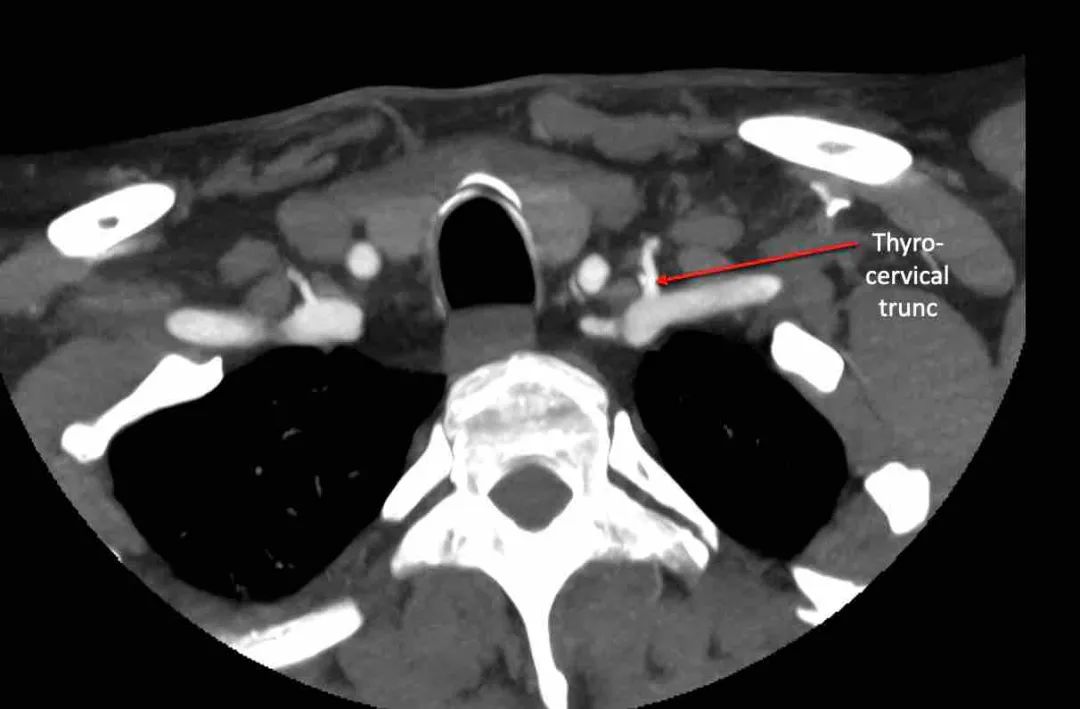

颈横动脉

滚动浏览图像,查看颈横动脉的解剖结构。